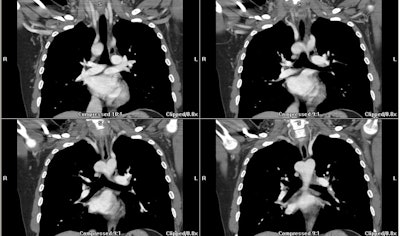

Right aortic arch with aberrant left subclavian artery:

In this patient with a right arch the left subclavian artery arises as the last branch from a large diverticulum (white arrow)